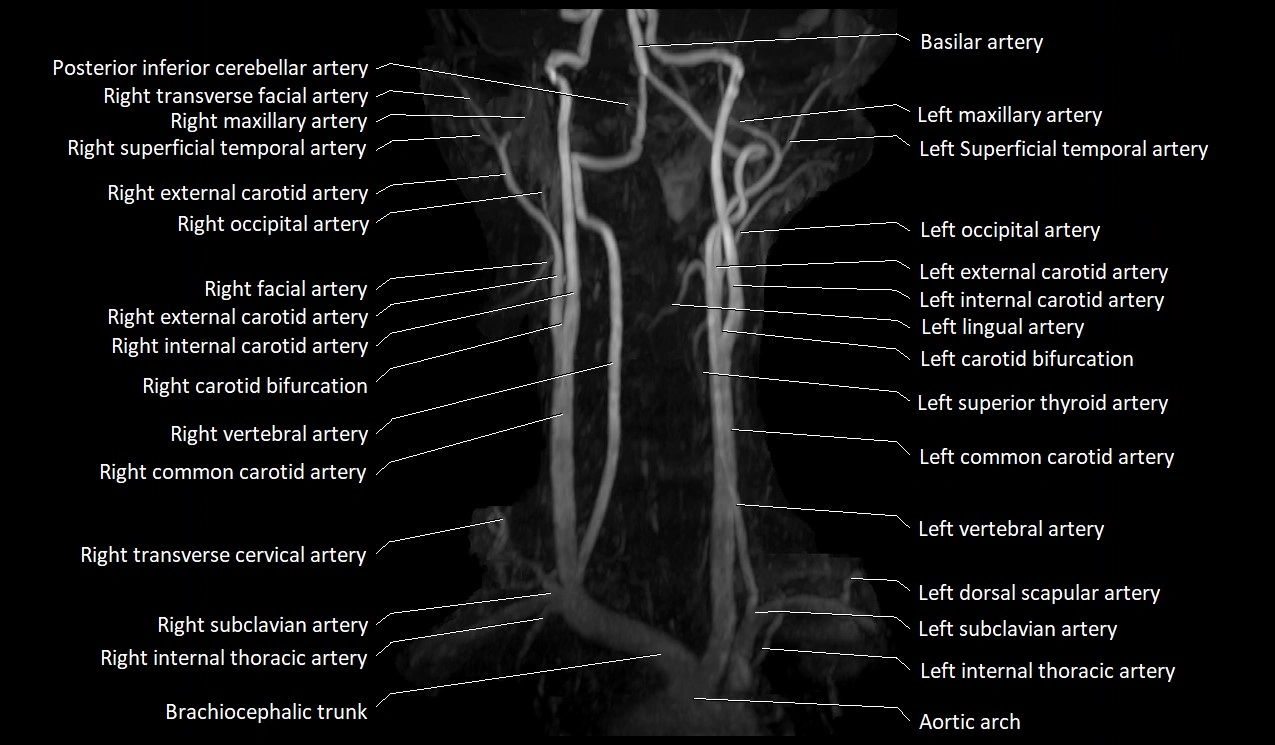

MRI images

image

CT image